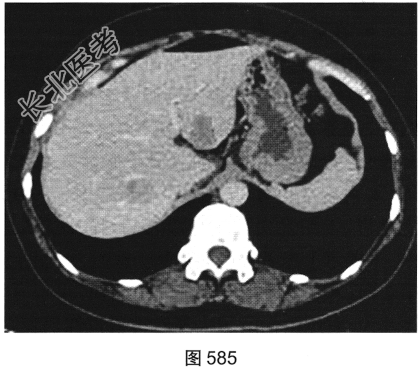

患者女性,38岁,因“间断性下腹部疼痛1周”入院。既往:否认肝炎、结核病史。查体:下腹部压痛。患者行腹部CT检查,见图582~图589。

- 多项选择题4.[提示]肠镜活检病理:中分化腺癌。糖链抗原724: 46.46U/ml,癌胚抗原292.61ng/ml, 糖链抗原242:58.13U/ml, 糖链抗原199:65.78U/ml。结合影像、临床、实验室检查及镜检病理结果, 该患者术前诊断应考虑为( )

A、直肠癌,伴肝脏炎性假瘤,右侧附件转移瘤

B、直肠癌,伴肝脏转移瘤及右侧附件转移瘤

C、直肠癌,伴肝脏转移瘤,右侧附件囊腺瘤

D、直肠癌,伴肝脏转移瘤,右侧附件囊腺癌

E、直肠癌,伴肝脏转移瘤.右侧附件子宫内膜异位症

F、直肠癌,伴肝脏炎性假瘤,右侧附件囊腺瘤